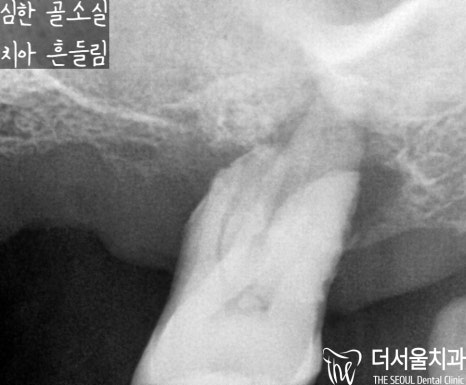

20번대 또한 마찬가지로

심하게 뼈를 잃게 되었으며,

그 영향으로 치아 흔들림이

나타날 수밖에 없었습니다.

30번대 어금니 또한 마찬가지,

뿌리 끝에 염증이 심하여

뼈가 사라져 치아 흔들림이